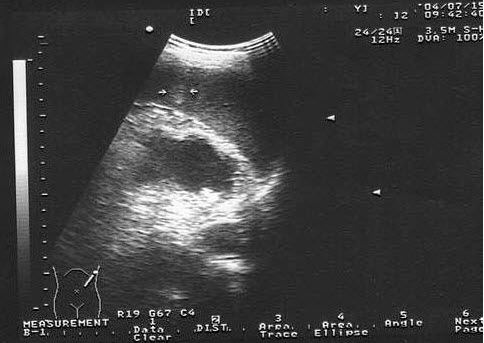

53、单项选择题

男性,4岁,因左肾区不适就诊,无外伤史,无发热,左腹部可扪及肿块。根据其声像图,可能的诊断为()

A.肾母细胞癌

B.急性肾炎

C.肾血管平滑肌脂肪瘤

D.肾脓肿

E.肾癌